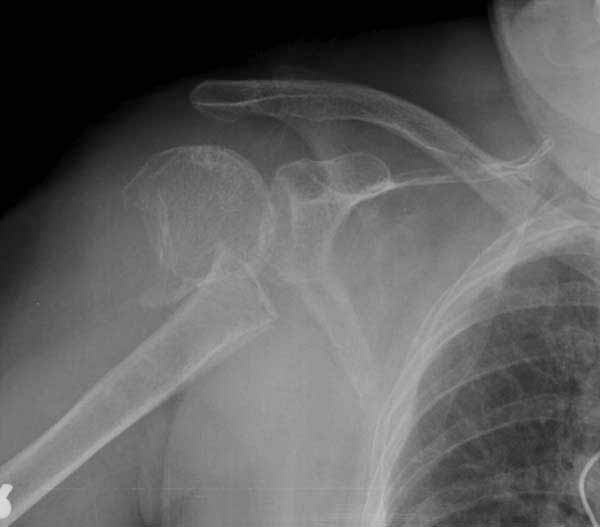

Здесь результат похожего случая, больная 87 лет, отягощенная сердечными делами и два года назад установка pacemaker и нескольких стентов. На третий день, сегодня утром сделали операцию. Послеоперационный псевдовывих связанный с релаксацией мышц и общим обезболиванием.

Имя     : humerus fx injury pacemaker.jpg

Тип     : image/jpg

Размер  : 27737 байтов

Описание: отсутствует

Url     : http://weborto.net:8080/pipermail/ortho/attachments/20110611/5927b955/attachment-0006.jpg